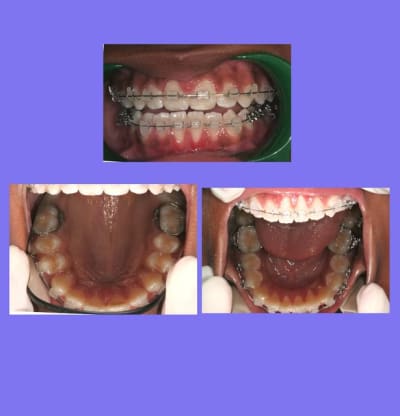

Voici un cas de béance associé à un Pb. paro sur 31/41

Est-ce qu’un traitement ODF. ne vas pas aggraver cette perte de gencive attaché (et osseuse),

et faut-il faire des extractions pour replacer 31/41 dans le massif osseux et arrêter cette récession ?

Fermeture de la béance par reformage des arcades tout en surveillant 31/41 que je traite par surfaçages et Kayes tous les mois

je prescris une brosse chirurgicale pour 31/41, la motivation de l’enfant et des parents est excellente

A suivre